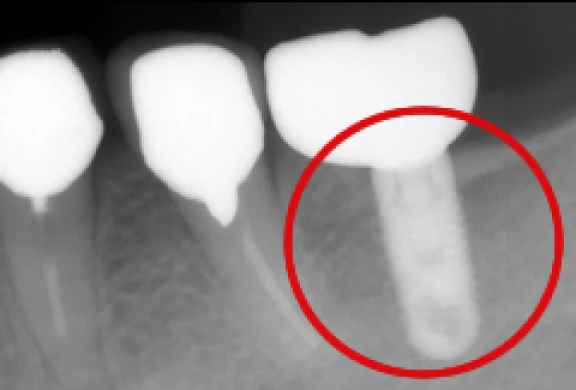

インプラント

自分の歯のような噛み心地を

歯科用CTによる精密診断を行い、お口の中の状態をしっかり把握させていただいた上で、適応のある方は院内にてインプラント治療を行います。

歯を失って再びご自身の歯のような噛み心地をご希望の方は、ご相談いただきたいと思います。

- 歯科用CT(タカラベルモント社BEL-X(ベルクロス))を設置しています。当院で撮影・画像診断を行い、院長自らが手術を行いますので、安心してご相談下さい。

- 当院ではHA(ハイドロキシアパタイト)インプラントを採用しています。

上部構造の装着

-

歯間部のインプラント

(上部構造の装着)